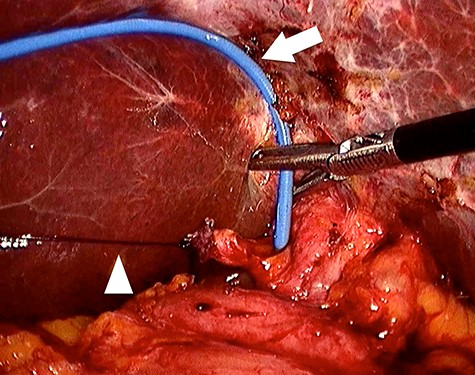

With the patient in supine position, the trocars were placed as per the American technique of LC. After releasing lax adhesions, the remaining cystic duct was recognized and individualized from the CBD with cold scissors. Once isolated, a lateral incision in the cystic stump was made for CBD exploration (Fig. 3). Under radiological guidance, the clip was successfully removed through the cystic duct with endoscopic hose-type biopsy forceps (Fig. 4). A control cholangiography confirmed CBD clearance (Fig. 5). At the end of the procedure, the metallic clip was removed from the abdominal cavity (Fig. 6), and the remnant cystic stump was secured with a PDS Endoloop Ligature in order to avoid any future migration (Video 1 shows our technique). The patient recovered uneventfully and was discharged 3 days after surgery.

Four trocars were used, one in the umbilicus (12 mm), another in the epigastrium (5 mm) and two in the right hypochondrium (5 mm). An Endoloop ligature (arrowhead) is placed in the isolated cystic stump and exteriorized in the right hypochondrium for traction. This facilitates the incision in the cystic stump and the transcystic biliary exploration with endoscopic hose-type biopsy forceps (arrow).